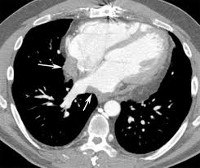

При постановке диагноза мезотелиомы перикарда используются данные рентгенографии грудной клетки, мультиспиральной КТ, магнитно-резонансной томографии сердца, ПЭТ, пункции перикарда с морфологическим исследованием экссудата, торакоскопии. Дополнительно проводятся электрокардиография, эхокардиография, радиоизотопное сканирование сердца.

Рентгенография грудной клетки при мезотелиоме перикарда помогает выявить наличие выпота и его причину - опухоль; КТ и МРТ сердца - оценить наличие и глубину инвазии опухолевого процесса: прорастание злокачественного новообразования в ткани сердца или органы грудной клетки. Большинство мезотелиом ПЭТ-позитивны, поэтому в последнее время для выявления этих опухолей часто применяют ПЭТ сердца с фтордезоксиглюкозой для определения микрометастазов в области перикарда.